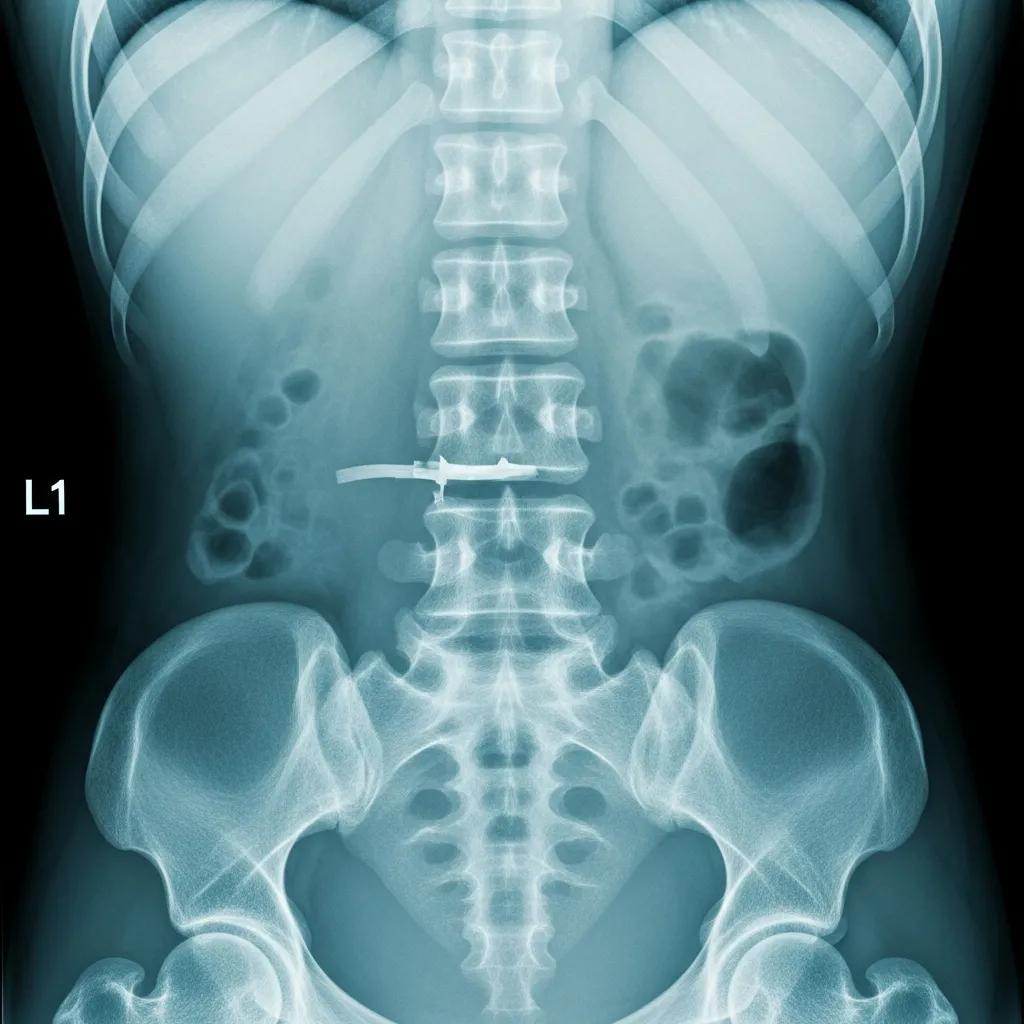

X-Ray image of the lumbar spine showing bone structures and potential fractures

X-Ray imaging diagnoses lower back conditions by providing clear images of the bony structures of the spine. Patients typically undergo a simple preparation process, which may include removing clothing or jewelry that could interfere with the imaging. X-Rays can identify conditions such as fractures, arthritis, and spinal alignment issues. Compared to MRI and CT scans, X-Rays are quicker and less expensive, making them a common first step in the diagnostic process.